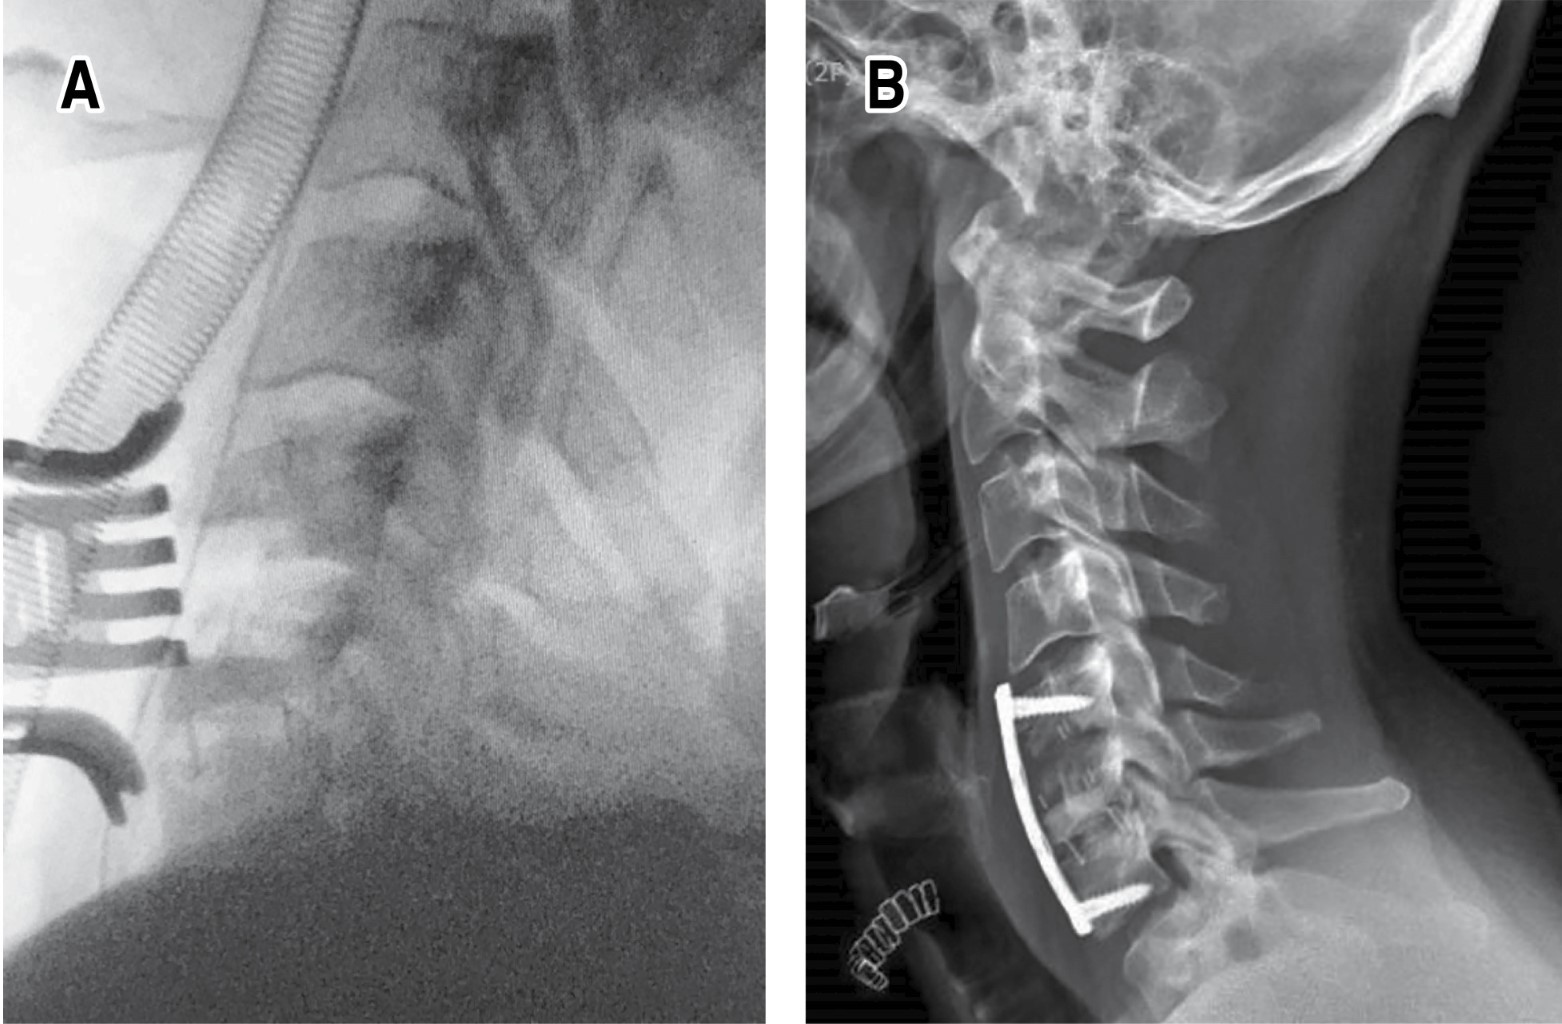

Introduction: cervical disc arthroplasty as a surgical treatment of spondylosis is a technique that has gained popularity in recent years with the advantage of maintaining movement and reducing the development of adjacent segment disease. Despite this, it is not free of complications, one of the least frequent being implant dislocation, with very few official reports in the global literature. A case report of a Baguera C type prosthesis is presented, a bibliographic review is carried out covering the different prosthetic devices that have an official report in the literature, frequencies, associated factors and treatment used are analyzed. Clinical case: 30-year-old male undergoing surgery for long-standing neck pain and myelopathy secondary to C5-C6 disc herniation and C6-C7 spondylosis. Hybrid cervical arthroplasty was performed with placement of a Baguera C disc prosthesis at C5-C6 and a CeSPACE interbody spacer at C6-C7. 13 months later he returned to the clinic with pain and refractory symptoms, X-rays were taken showing posterior dislocation of the implant. Revision surgery was performed, removing the implant, placing an interbody spacer plus bone graft, and placing an anterior locked plate with complete remission of symptoms. Conclusions: prosthetic dislocation is rare, the literature reports few cases, this being the first related to the Baguera C prosthesis, surgical treatment is imperative. The female sex and the C5-C6 level are the most affected, the previous variant is the most common. Careful placement and proper selection of the implant size are the most important factors to take into account and reduce the chances of failure. When it occurs, arthrodesis is usually the most used option with favorable results.

Figure 3

Figure 4